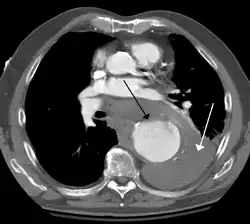

A thoracic aortic aneurysm is an aortic aneurysm that presents primarily in the thorax.

A thoracic aortic aneurysm is the "ballooning" of the upper aspect of the aorta, above the diaphragm. Untreated or unrecognized they can be fatal due to dissection or "popping" of the aneurysm leading to nearly instant death. Thoracic aneurysms are less common than an abdominal aortic aneurysm.[2] However, a syphilitic aneurysm is more likely to be a thoracic aortic aneurysm than an abdominal aortic aneurysm. This condition is commonly treated via a specialized multidisciplinary approach with both vascular surgeons and cardiac surgeons.